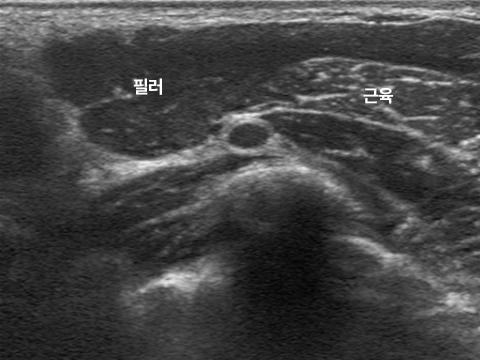

가슴필러, img img

꼭 제거해야 하는 이유

가슴필러 제거 수술 방법

• img img

01

초음파 검사를 통해

필러의 위치 파악

초음파로 보면 큰 덩어리의 필러가 모여 있기 때문에 모두 제거하면 되지만

문제는 유방조직에 끈끈하게 붙어 있는 필러입니다.

이를 무리하게 긁어내면 본인의 정상 유방조직에 손상이 갈 수 있으므로

유방조직의 손상은 최소화 시키면서 필러를 최대한 제거할 수 있는

섬세한 기술

이 필요합니다.

• 필러가 근육 위에 뭉쳐져 있는 상태

img img

<제거 수술 전>

• 필러가 깨끗하게 제거 된 상태

img

<제거 수술 후>